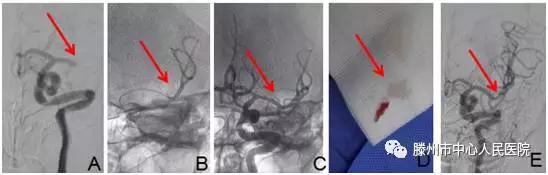

明確診斷為“腦栓塞”后,告知患者家人病情,建議機械取栓治療?;颊呒胰送夂螅痹\科護士迅速護送病人于9:35分進入介入手術(shù)室。再次與患者溝通病情并積極行手術(shù)準備。9:40股動脈穿刺成功,造影見左側(cè)大腦中動脈M1段以遠閉塞(圖A),10點10分支架微導管到位(圖B)

10點19分Soltaire-AB支架到位打開后血流恢復(圖C),患者癥狀明顯減輕,等待5分鐘后,支架取出長條狀血栓(圖D),患者癥狀完全緩解,言語及肢體力量完全恢復正常。觀察10分鐘病情無反復,再次造影左側(cè)大腦中動脈顯影完全正常(圖E),結(jié)束手術(shù),安返病房。